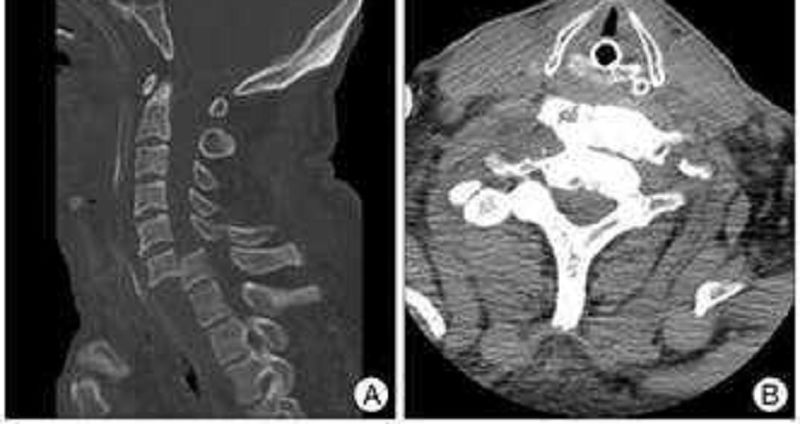

Welche Erkrankung beschreibt dieses Bild?

Skoliose

Spondylolisthese bei Spondylolyse

Morbus Scheuermann

Spondyloptose